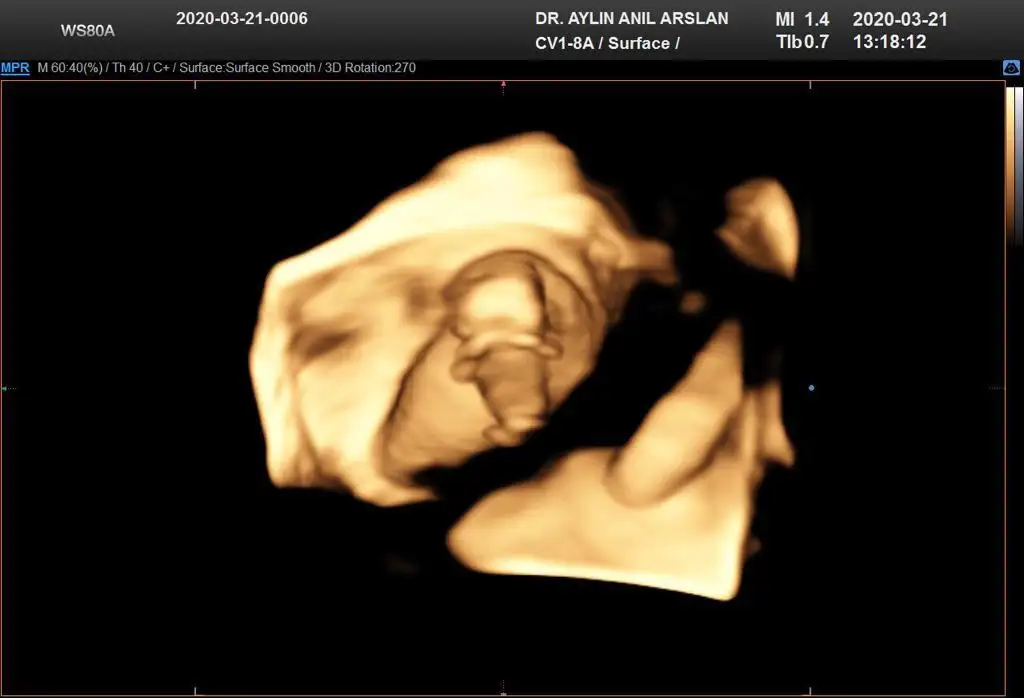

11+3 ama cok net değil gibi sanki yinede Bi tahmin isterim daha 5 hafta sonra öğrencez mecbur 😪

• IMG-20200321-WA0011.webp

IMG-20200321-WA0011.webp

25,8 KB · Görüntüleme: 41